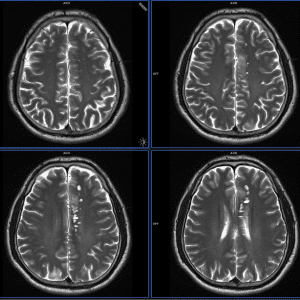

Rộng khoang quanh mạch